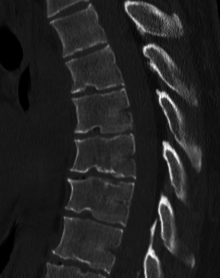

Diagnosis is typically by medical imaging.